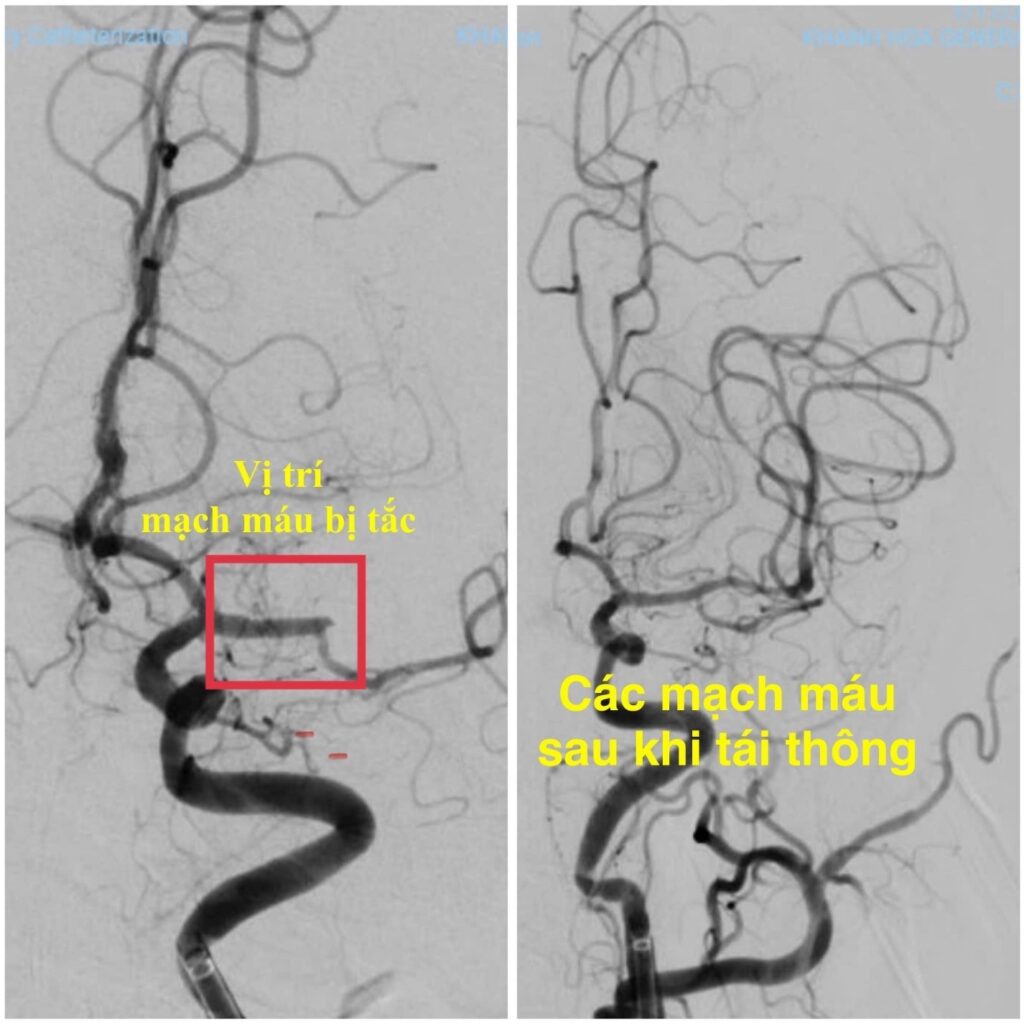

Ngay trong đêm, ê-kíp can thiệp mạch não Khoa Đột quỵ đã nhanh chóng tiến hành can thiệp lấy huyết khối và tái thông hoàn toàn động mạch não giữa trái bằng hệ thống máy DSA. Thủ thuật được thực hiện khẩn trương, chính xác, đảm bảo an toàn cho người bệnh.

Chỉ sau 24 giờ can thiệp, bệnh nhân cải thiện ngoạn mục, tỉnh táo, giao tiếp trở lại bình thường, chỉ còn yếu nhẹ nửa người phải với sức cơ 4/5. Kết quả CT sọ não kiểm tra cho thấy tổn thương nhỏ, khu trú vùng vành tia cũ, không ghi nhận biến chứng xuất huyết. Sau vài ngày bệnh nhân phục hồi gần như hoàn toàn.